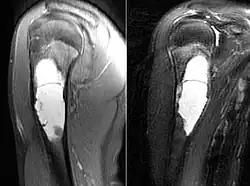

MRI scan: simple bone cyst humerus of a 13 year old boy

Magnetic resonance imaging scans are used to identify the precise location of the cyst, to see how aggressive the disease is, and to determine the actual shape and size.[4] The MRI uses a combination of magnets and radio-frequencies to produce various detailed, computerized images of the cyst and its surrounding body structures.[4]